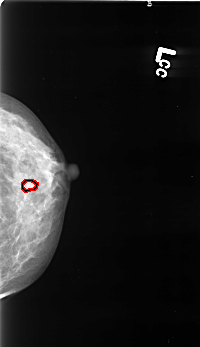

B_3418_1.LEFT_CC

FILE: B_3418_1.LEFT_CC.OVERLAY

TOTAL_ABNORMALITIES 1

ABNORMALITY 1

LESION_TYPE CALCIFICATION TYPE PUNCTATE-AMORPHOUS DISTRIBUTION CLUSTERED-LINEAR

ASSESSMENT 4

SUBTLETY 3

PATHOLOGY BENIGN

TOTAL_OUTLINES 1

BOUNDARY